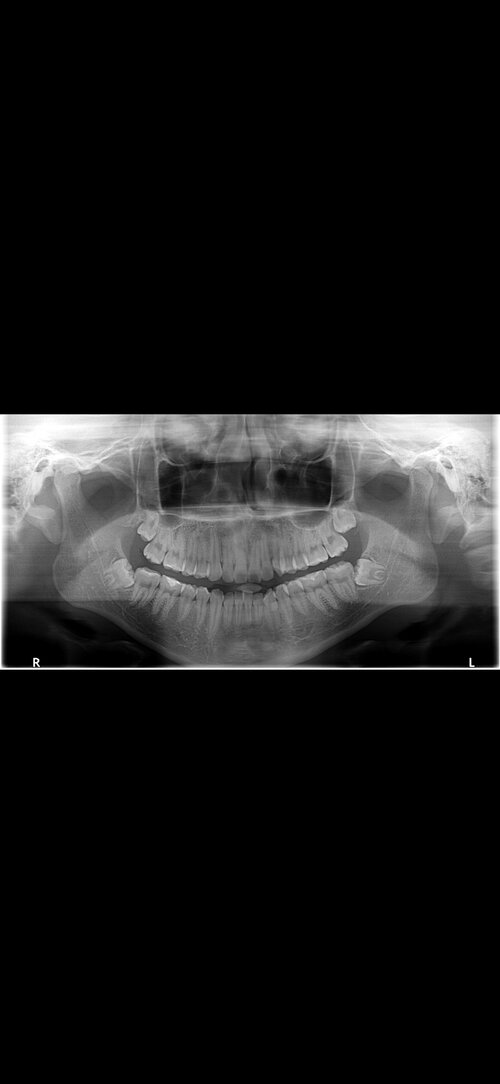

For context I have some crowding with slight overbite/deepbite. I've gone to my orthodontists and they plan to give me traditional braces or invisalign with class 1 elastic for a small amount of time. They said they might use a forsus as well but im not completely sure. I'm unsure of what to do and how this would affect me.